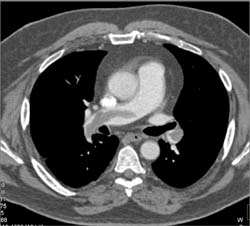

Pulmonary Embolism